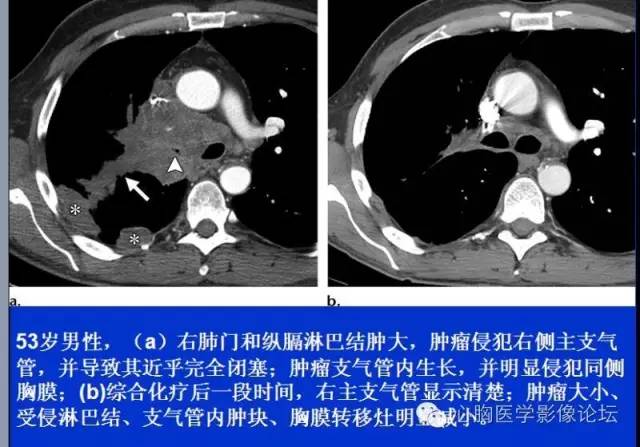

肺癌晚期影像图片,肺癌影像图片晚期

【病例】小细胞肺癌1例ct影像表现